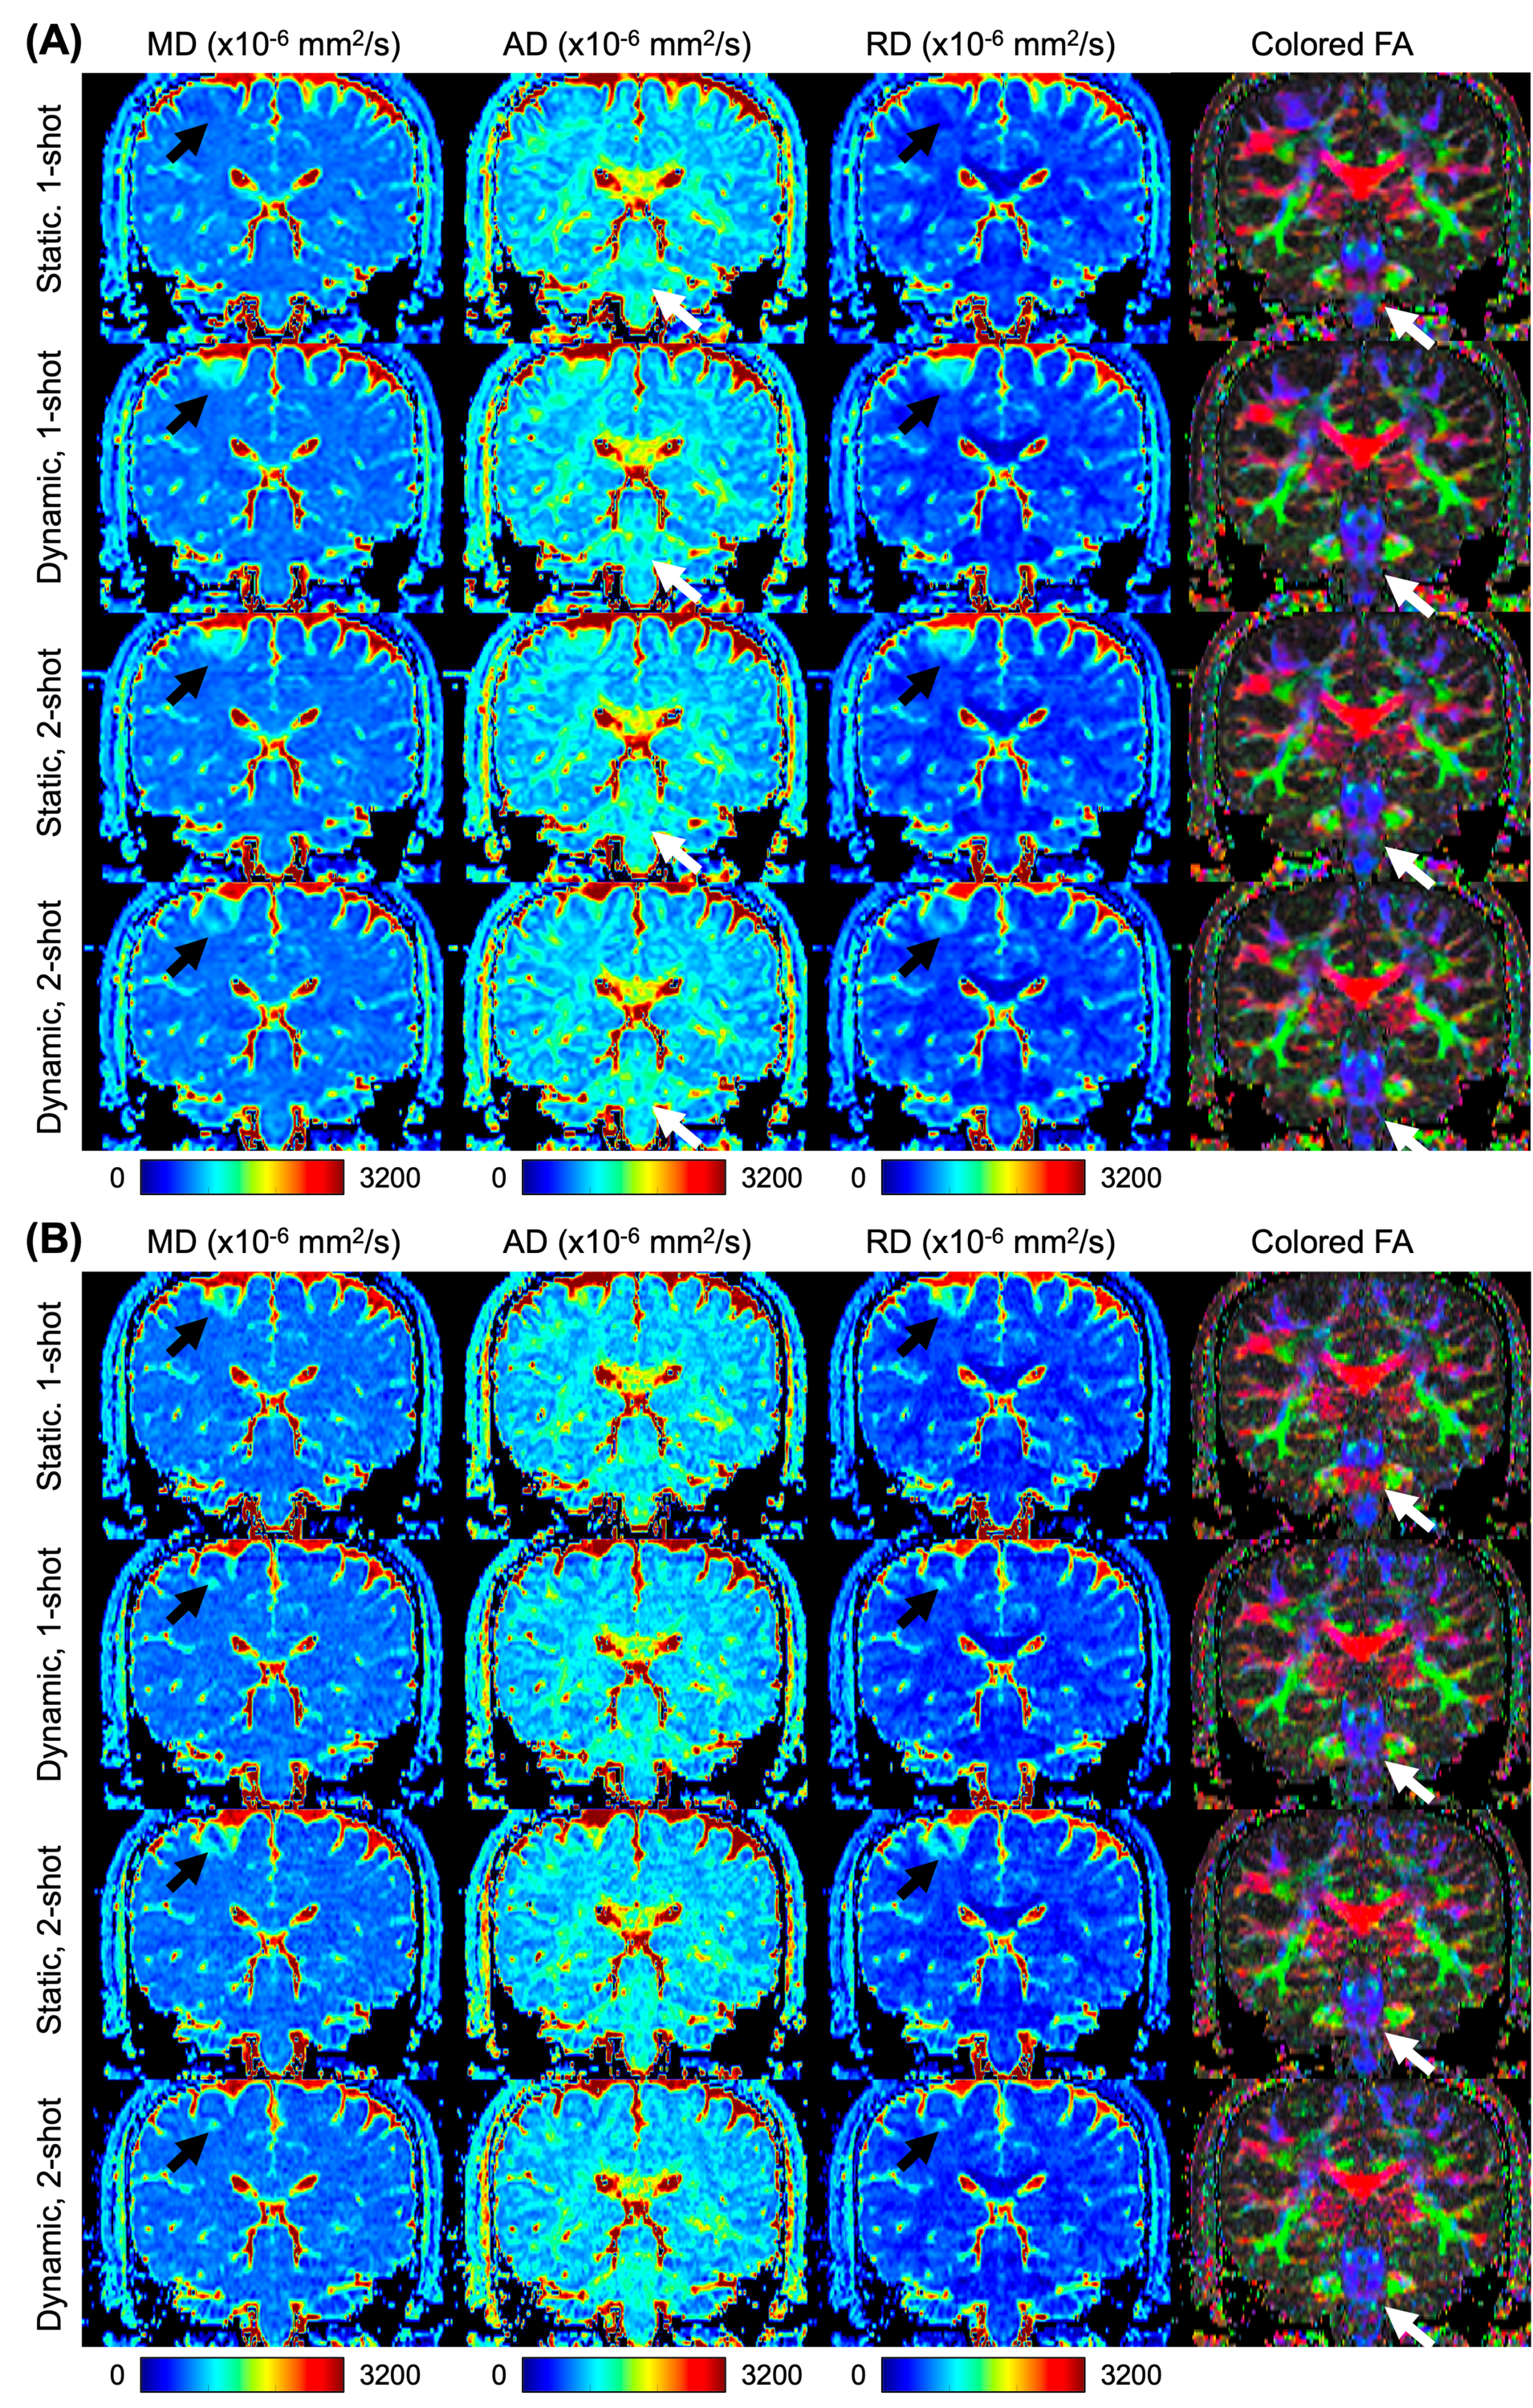

Figure 6 shows the MD/AD/RD/FA of PGSE DTI of a healthy volunteer acquired at 2 x 2 x 2 (Figure 6A) and 1 x 1 x 2 (Figure 6B) resolutions using different field shimming approaches. The brainstem showed similar AD and FA across dynamic 1-shot acquisition, static 2-shot acquisition, and dynamic 2-shot acquisition, which differ from AD and FA estimated from the static 1-shot acquisition, as pointed by the white arrows. Cerebral cortex and white matter at the superior regions of the brain also showed similar MD, AD,RD, and FA across dynamic 1-shot acquisition, static 2-shot acquisition, and dynamic 2-shot acquisition, which differ from that estimated from the static 1-shot acquisition, as pointed by the black arrows. The effect of -induced image shift and distortion on the diffusivity is more discernible at 1 x 1 x 2 resolution, compared to 2 x 2 x 2 . For example, the colored FA in the posterior brain regions (as pointed by the white arrows in Figure 6B) showed blue color in dynamic 1-shot acquisition, static 2-shot acquisition, and dynamic 2-shot acquisition, indicating white matter tracts in the brainstem along superior-inferior directions. In comparison, the colored FA in the same regions in static 1-shot acquisition showed red color, indicating white matter tracts in the cerebral peduncle which was misplaced in the image due to large .